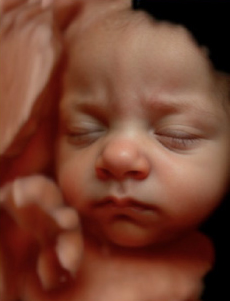

Experimenta la última tecnología hiperrealista 8K, una imagen increíblemente detallada y realista de los rasgos de tu bebé, con una textura y definición que te sorprenderán.

Ecox Alicante ya cuenta con la posibilidad de ofrecer a todos los futuros papis madrileños una experiencia inolvidable gracias a la ecografía 5D y el novedoso hiperrealismo 8K.

Esta nueva tecnología nos permite ofreceros a los futuros papás las imágenes de mayor calidad para que disfrutéis de la experiencia como nunca antes había sido posible.